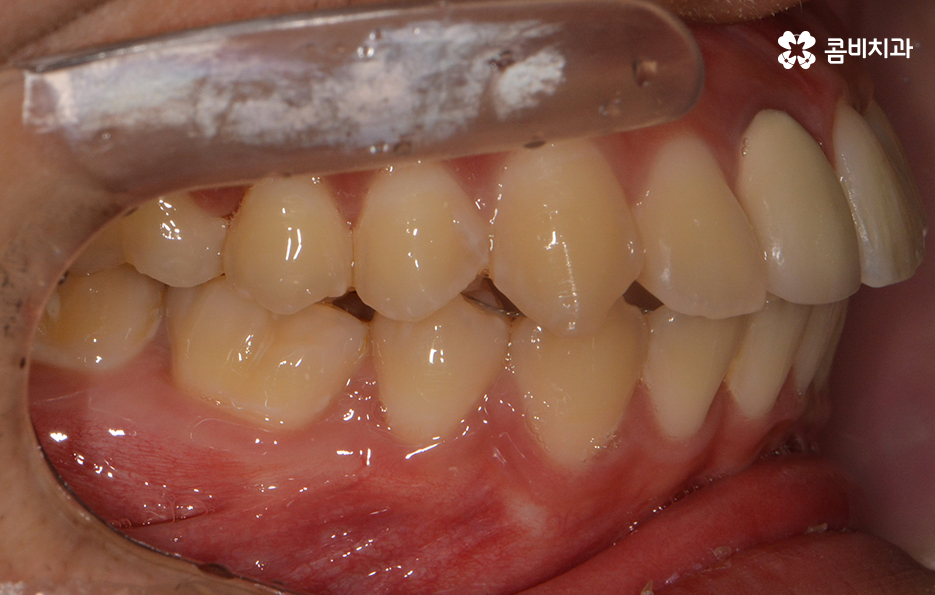

전체적으로 치열이 가지런한 편이지만 덧니가 하나 정도

눈에 띄게 있는 경우에는 귀여운 포인트로 여기는 경우도

있지만 덧니가 치아 곳곳에 심한 경우에는 웃을 때마다

콤플렉스를 느끼거나 치아 기능상의 문제, 청결 관리의

어려움 등을 느끼시는 분들도 많을 거예요.

덧니가 심한 경우에는 음식물이 치아 사이에 끼기 쉽고

심미적으로도 좋지 않기 때문에 덧니교정을 통해서

치열을 가지런하게 재배치하는 것이 필요할 수 있는데요.

왼쪽이 윗니이고 오른쪽이 아랫니인데 치열의 불규칙함이

심한 편이다 보니 평소 음식물이나 치석이 끼기 쉬운 환경이

되고 이러한 구강 환경이 지속된다면 충치와 잇몸질환의 발생률이 높아질 수 있어요.